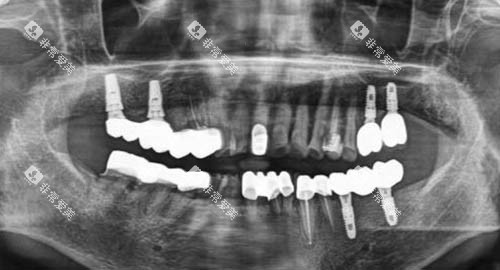

如智能化口腔全景机、口腔CT等,可以清晰地显示患者口腔内部的结构和病变情况,为医生的诊断和治疗提供更准的依据。

例如,在牙齿种植领域,医生们能够根据患者的口腔状况和身体条件,制定个性化的种植方案,确保种植结果的稳定性和美观性。